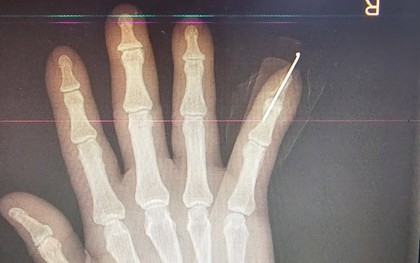

Nối thành công ngón tay đứt lìa cho bệnh nhân

Bệnh viện Thống Nhất (Đồng Nai) vừa phẫu thuật vi phẫu nối thành công ngón tay đứt lìa cho bệnh nhân 63 tuổi bị tai nạn lao động, giúp bảo tồn chức năng bàn tay.